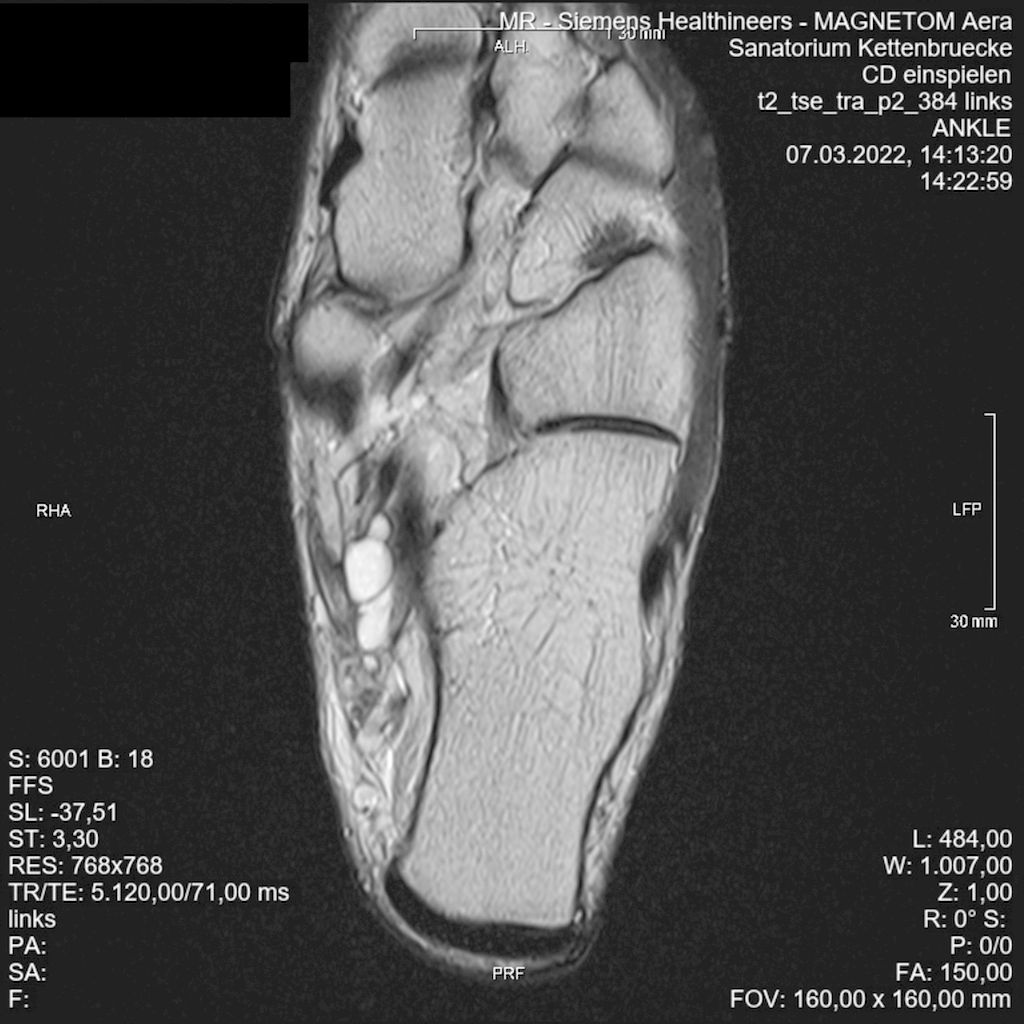

Abb. 1: T2-gewichtete MRT-Aufnahme des Fußes: raumforderndes septiertes Ganglion (Pfeil) im Tarsaltunnel mit Kompression des Gefäßnervenbündels (Stern)

Die Röntgenaufnahme des Sprunggelenks im Stehen in zwei Ebenen ist der Standard zur Beurteilung von Fehlstellungen, Frakturen und eventuell vorliegenden knöchernen Raumforderungen im Bereich des Tarsaltunnels. Die Sonografie ist eine günstige und breit verfügbare Untersuchungstechnik. Mit ihr lassen sich direkte Zeichen der Nervenkompression mit fokaler Vergrößerung der Faszikel und Änderungen der Echogenität gut darstellen.5 Die Magnetresonanztomografie ist der Goldstandard in der weiterführenden Schnittbildgebung zur Beurteilung vorliegender Raumforderungen mit Bedrängung des Nervus tibialis (Abb.1).